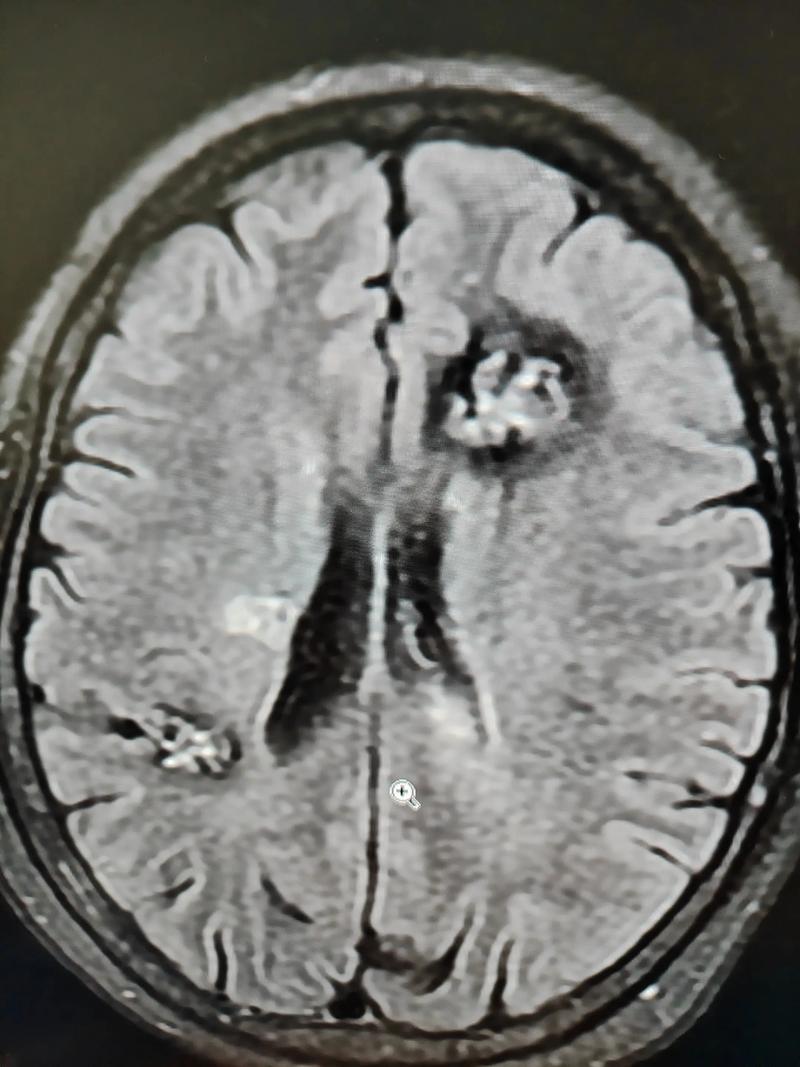

这是最常见的原因,脑梗和脑肿瘤在CT或MRI(磁共振)影像上有时会表现相似,都表现为“脑内占位性病变”或“异常信号”。

- 急性期脑梗:在发病后的最初几天,由于脑组织急性水肿,影像上可能看起来像一个肿瘤,周围有明显的占位效应,医生称之为“假性肿瘤”。

- 脑梗后的出血性转化:有些脑梗患者,特别是大面积脑梗,在治疗过程中梗死区域可能会因为血流再通等原因发生出血,形成“出血性脑梗”,这在影像上也会表现为混杂信号的占位性病变,容易与肿瘤内出血混淆。

当影像学检查发现一个“可疑病灶”时,医生需要结合病史、发病速度、影像特征变化,甚至进行活检来最终判断,究竟是脑梗的演变、出血转化,还是一个真正的脑肿瘤。

- 影像鉴别:影像学上有时会表现相似,需要专业医生仔细鉴别,不要因为看到报告上的“占位”或“异常信号”就过度恐慌,它很可能是脑梗本身的表现或并发症。